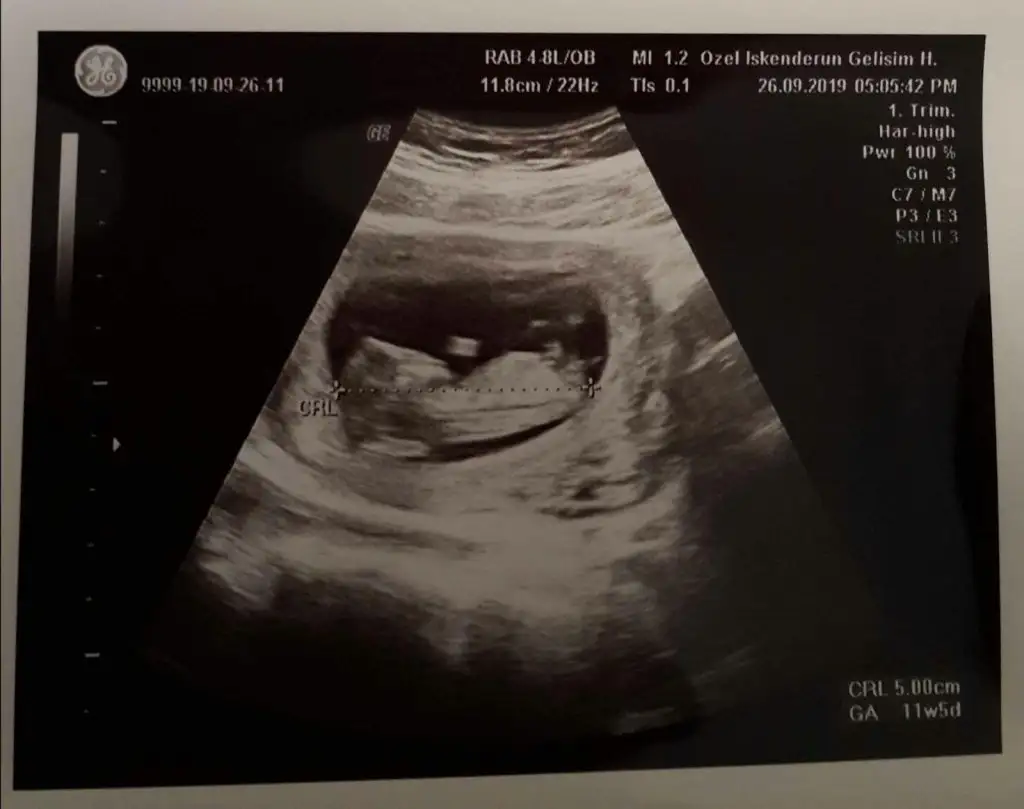

Bu da erkek gibiArkadaşlar arkadaşımın bebeğinede bakabilirmisiniz kızmı erkekmi diye 11 hafta 5 günlükEki Görüntüle 2543755

Eki Görüntüle 2543860 Merhabalar.Ikra meyra cim iyi akşamlar canım. Fotoğrafı yüklüyorum fikirlerinizi çok merak ediyorum :)